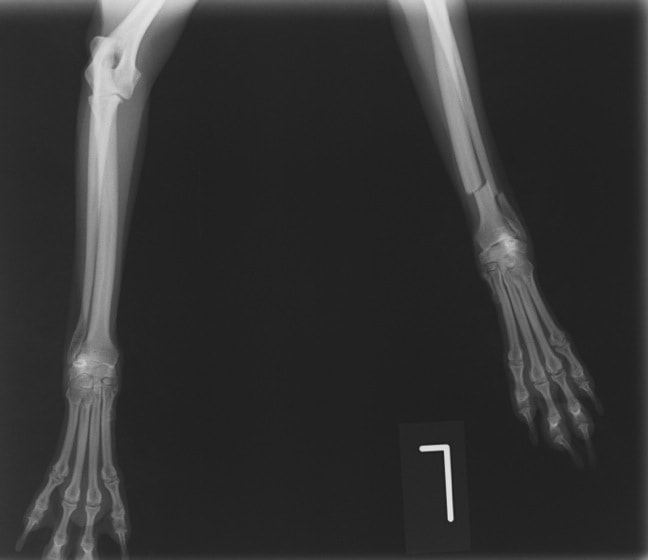

ペルシャ猫 11ヶ月齢 雄

他院にて左大腿骨遠位の成長板骨折(salter-harrisⅠ型)が認められており、治療相談を目的として来院。当院にて、キルシュナーワイヤーを用いたピンニングにより骨折部位の整復を行いました。術後の経過は良好で、現在も経過観察中です。

術前レントゲン

術後レントゲン